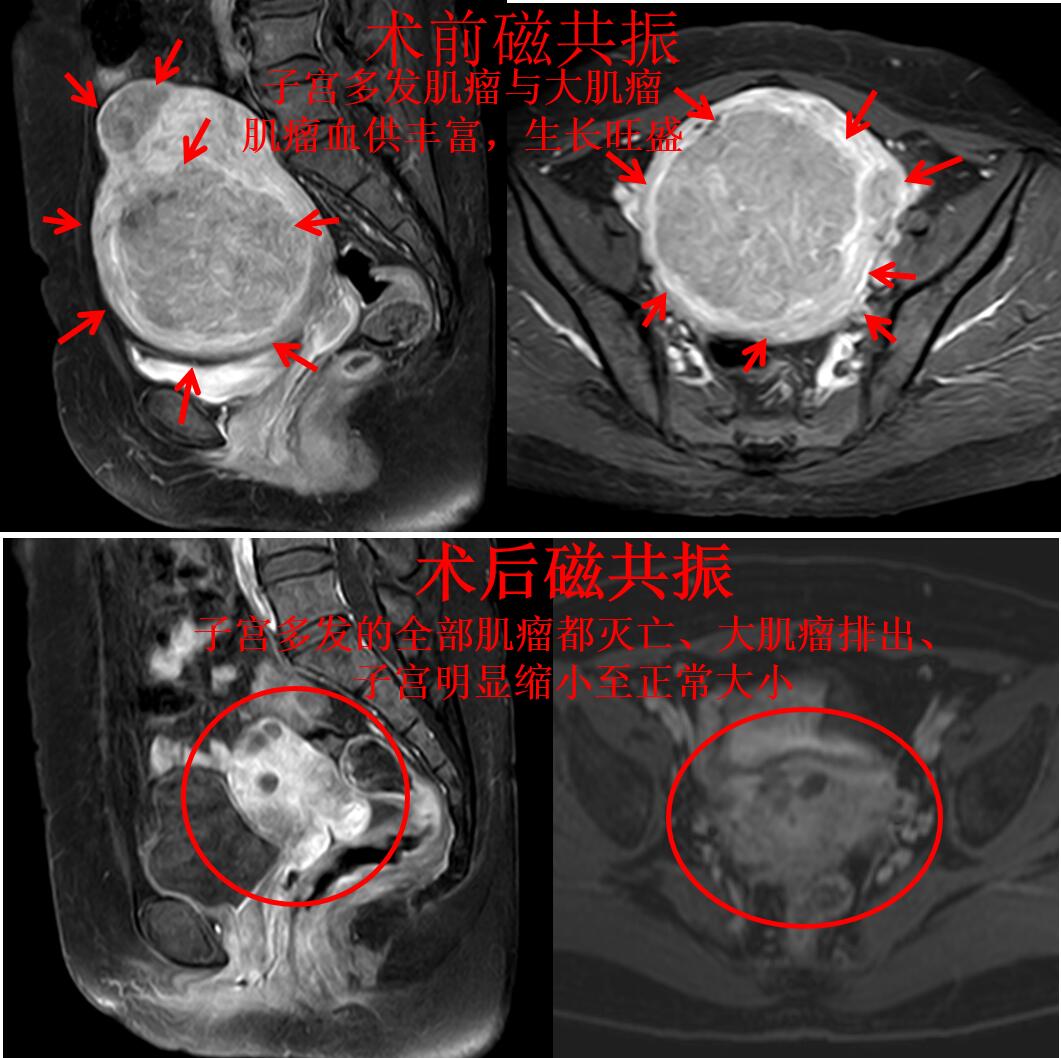

乔女士今年45岁,月经量过多已经5年多了,还一个月比一个月厉害,在当地医院超声检查发现是多发子宫肌瘤在作怪。这半年来月经量超多,例假多的时候基本一个小时换一张,贫血53g/L,还到医院输血治疗,月经量超多,贫血严重,好不容易补血到80g/L,一来例假马上打回原形,重度贫血。在当地医院只有切除子宫的方法。乔女士不能接受子宫切除,则来到我科就诊,门诊磁共振检查显示:子宫增大(136mm*101mm*109mm)、子宫多发肌瘤,最大肌瘤(106mm*95mm*89mm),如下图

随后乔女复查磁共振显示:子宫多发的全部肌瘤都灭亡、大肌瘤排出、子宫明显缩小了(如下图),真正的达到了一次打尽所有的肌瘤。